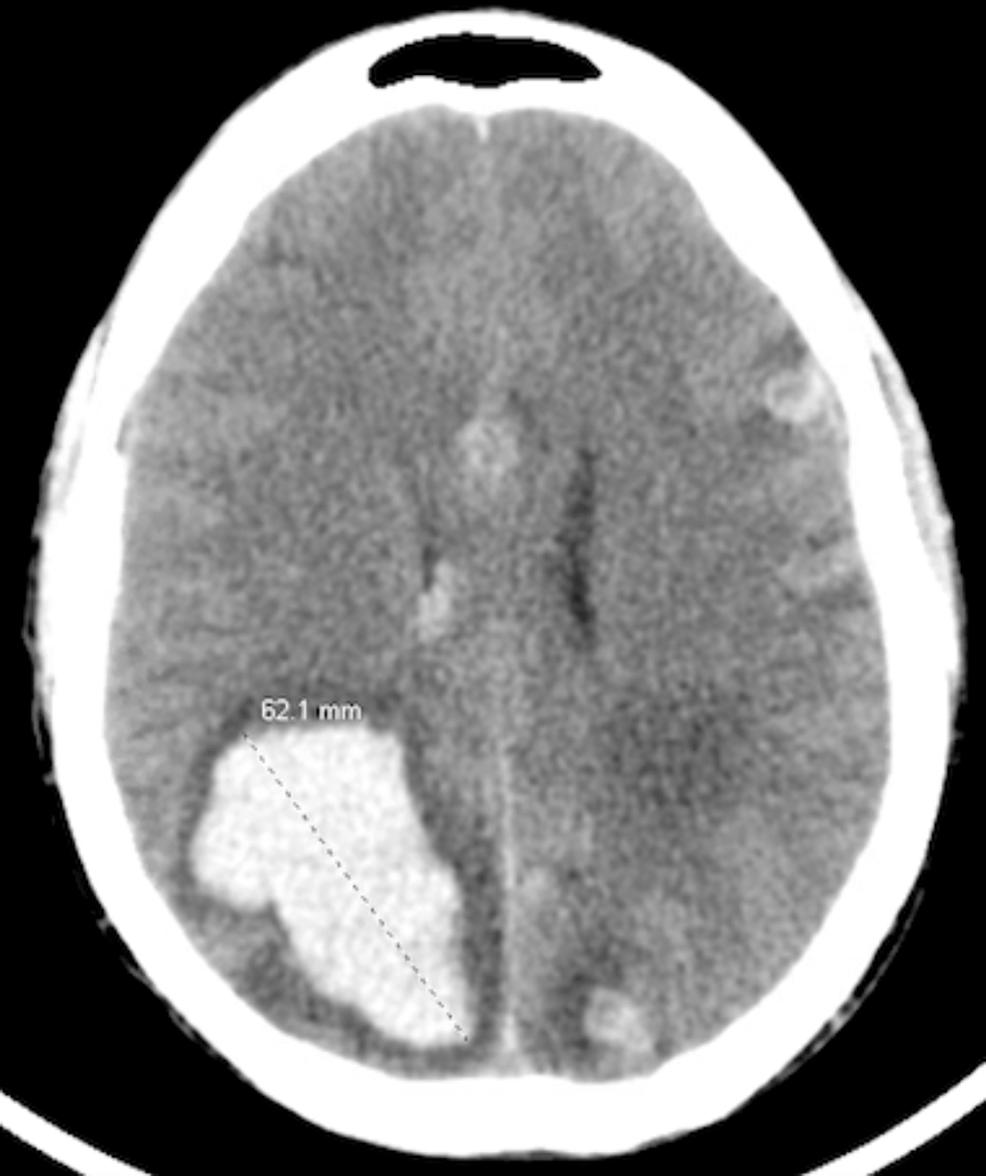

Brain CT of a young man with testicular germ cell tumor is showing Testicular Cancer Brain Metastases Common treatments for brain metastases from testicular primary cancers include surgical resection, whole brain radiation (wbrt), stereotactic radiosurgery (srs), or combinations of these methods. Testicular cancer with neurological symptoms indicates brain metastases. We found that brain tumors from testicular cancer are very rare, found in just 0.4% of the patients we studied. Testicular cancer with neurological symptoms indicates brain metastases.. Testicular Cancer Brain Metastases.